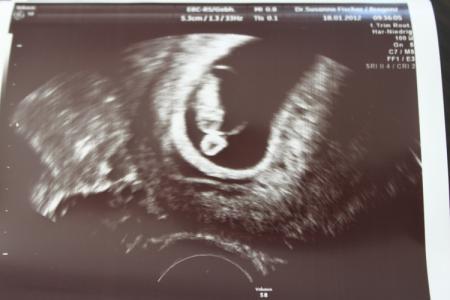

hab ihre den "rummmmmms" ghört? das war der Stein der mir um 9.45 uhr vom herzen gefallen ist :D ich durfte eine termingerecht entwickelte 1,31cm grosse erdnuss betrachten die mich vor glück zum weinen gebracht hat , auch jetzt gerade wieder :D das herzchen wummert ordentlich und ich darf nach 8 jahren wieder in den augustbus einsteigen ET bleibt der 31.08.2012 und mein nächster FA termin hab ich in 5 wochen da bin ich dann 13+0 ich danke euch für die vielen daumen lg katrin

Katrin das freut mich sehr für dich!! Sehr süßes Bild von deiner "Erdnuss"!!

Hatte den riesen Stein gehört...hi hi. Super, freut mich sehr für dich, dass alles in Ordnung ist. So ein tolles Bildchen und das in der 8. SSW.